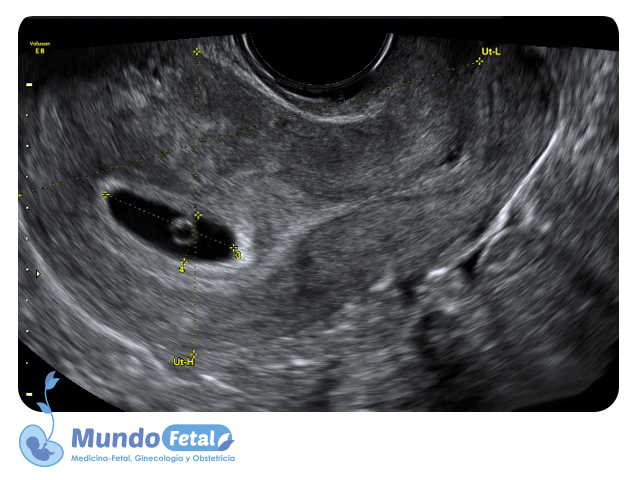

Ultrasonido Temprano 1er Trimestre (Menor 11 Semanas)

Estudio que nos permite la confirmación del embarazo, numero de bebes, valoración de líquido amniótico, placenta, vitalidad por medio de la frecuencia cardiaca, crecimiento armónico y edad gestacional estimada, descartando alguna complicación propia de esta edad.